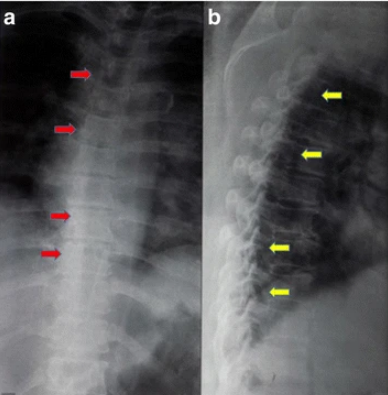

進(jìn)行了胸部X光檢查,結(jié)果正常(見圖1)。T1加強磁共振成像顯示,Th8和Th9椎體后方硬膜內(nèi)位置有一個規(guī)律性的低強度病變,主要位于左側(cè)。該病變壓迫了脊髓向左。在T2加強磁共振成像中,病變相對于正常脊髓具有等強度(圖2)。

1 胸腔區(qū)域、前后側(cè)和側(cè)面的普通X光片。a 前后視角顯示脊柱畸形及胸椎周圍的腫塊沉積過程(紅色箭頭)。b 側(cè)面圖顯示脊柱管某一水平處有退行性腫瘤沉積(黃色箭頭))